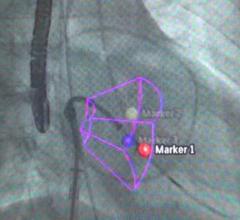

DePuy Synthes CMF (craniomaxillofacial) announced the launch of Trumatch CMF Solutions for facial reconstruction, orthognathic surgery, distraction and cranial reconstruction at the 2013 American Association of Oral and Maxillofacial Surgeons (AAOMS) annual meeting.